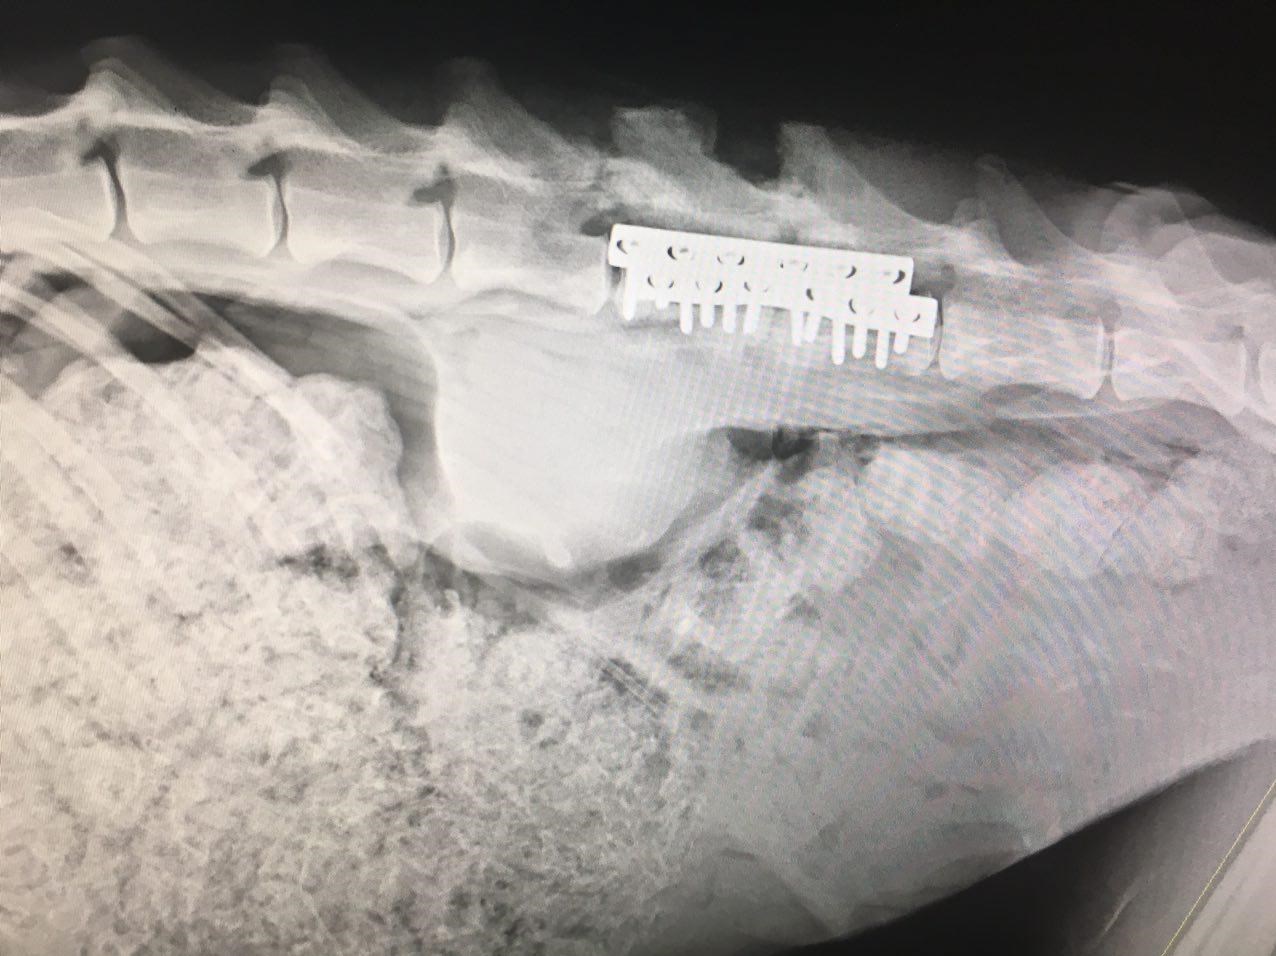

پلنگ انتقالی پس از انجام مرحله بیهوشی، به بخش تصویربرداری ارجاع و سپس تحت پرتونگاری جانبی ستون فقرات، قفسه صدری و نمای پشتی جانبی مهره ها قرار گرفت. پس از آن از بیمار خون گیری شد و جهت بررسی های هماتولوژی و بیوشیمیایی به آزمایشگاه تشخیص طبی بیمارستان ارسال گردید، ضمنا اولترا سونوگرافی شکم جهت بررسی وضعیت اندام های داخلی، بالاخص مثانه، انجام شد. پلنگ مورد نظر، با تشخیص جا به جایی مهره های چهار و پنج کمری، تحت عمل جراحی قرار گرفت. پس از انجام پروسه آماده سازی بیمار و با ملاحظات دقیق و پایش مداوم علایم حیاتی، ضمن ایجاد انسزیون پشتی – جانبی در محاذات مهره های آسیب دیده و جدا نمودن بافت های عضلانی و همبندی در هر طرف، مهره ها اکسپوز گردید. در سطح مفصلی فست ها، بافت همبندی هایپر تروف و وجود کالوس ترمیمی به دلیل اسلایدینگ و جا به جایی در محل، برداشته شد. بررسی دقیق از لامینای مهره ها، شکستگی وتغییرات پاتولوژی بافتی را حداقل در کورتکس خارجی نشان نداد و همچنین در سطح ماکروسکوپی واکنش های عفونت استخوانی در ساختار اطراف مهره مشاهده نگردید. سپس با جداسازی عضلات مجاور دو مهره چهارم و پنجم، جسم مهره مورد بررسی قرار گرفت و تغییرات شکستگی و جا به جایی در جسم مهره ها یافت نشد. سپس موضع مورد نظر با روش دیسترکشن به وسیله دیسترکتور مهره ای، ریداکشن جا به جایی و اسلایدینگ دو مهره نسبت به هم صورت پذیرفت، سپس تحت فلورسکوپی حین عمل به صورت بایلترال جسم مهره های آسیب دیده با پلیت استخوانی DCP و پیج های کورتیکال سلف تپ، استبلایز گردید. پس از تایید قرار گیری مناسب و دقیق پیج ها و پلیت ها و شستشوی سایت عمل با محلول حاوی آنتی بیوتیک وسیع الطیف (سفازولین) عضلات اپکسیال بخیه شد. سپس بافت زیر جلد و جلد با نخ قابل جذب بخیه گردید. پس از اتمام عملیات جراحی، رادیوگرافی بعد از عمل نیز تهیه شد.